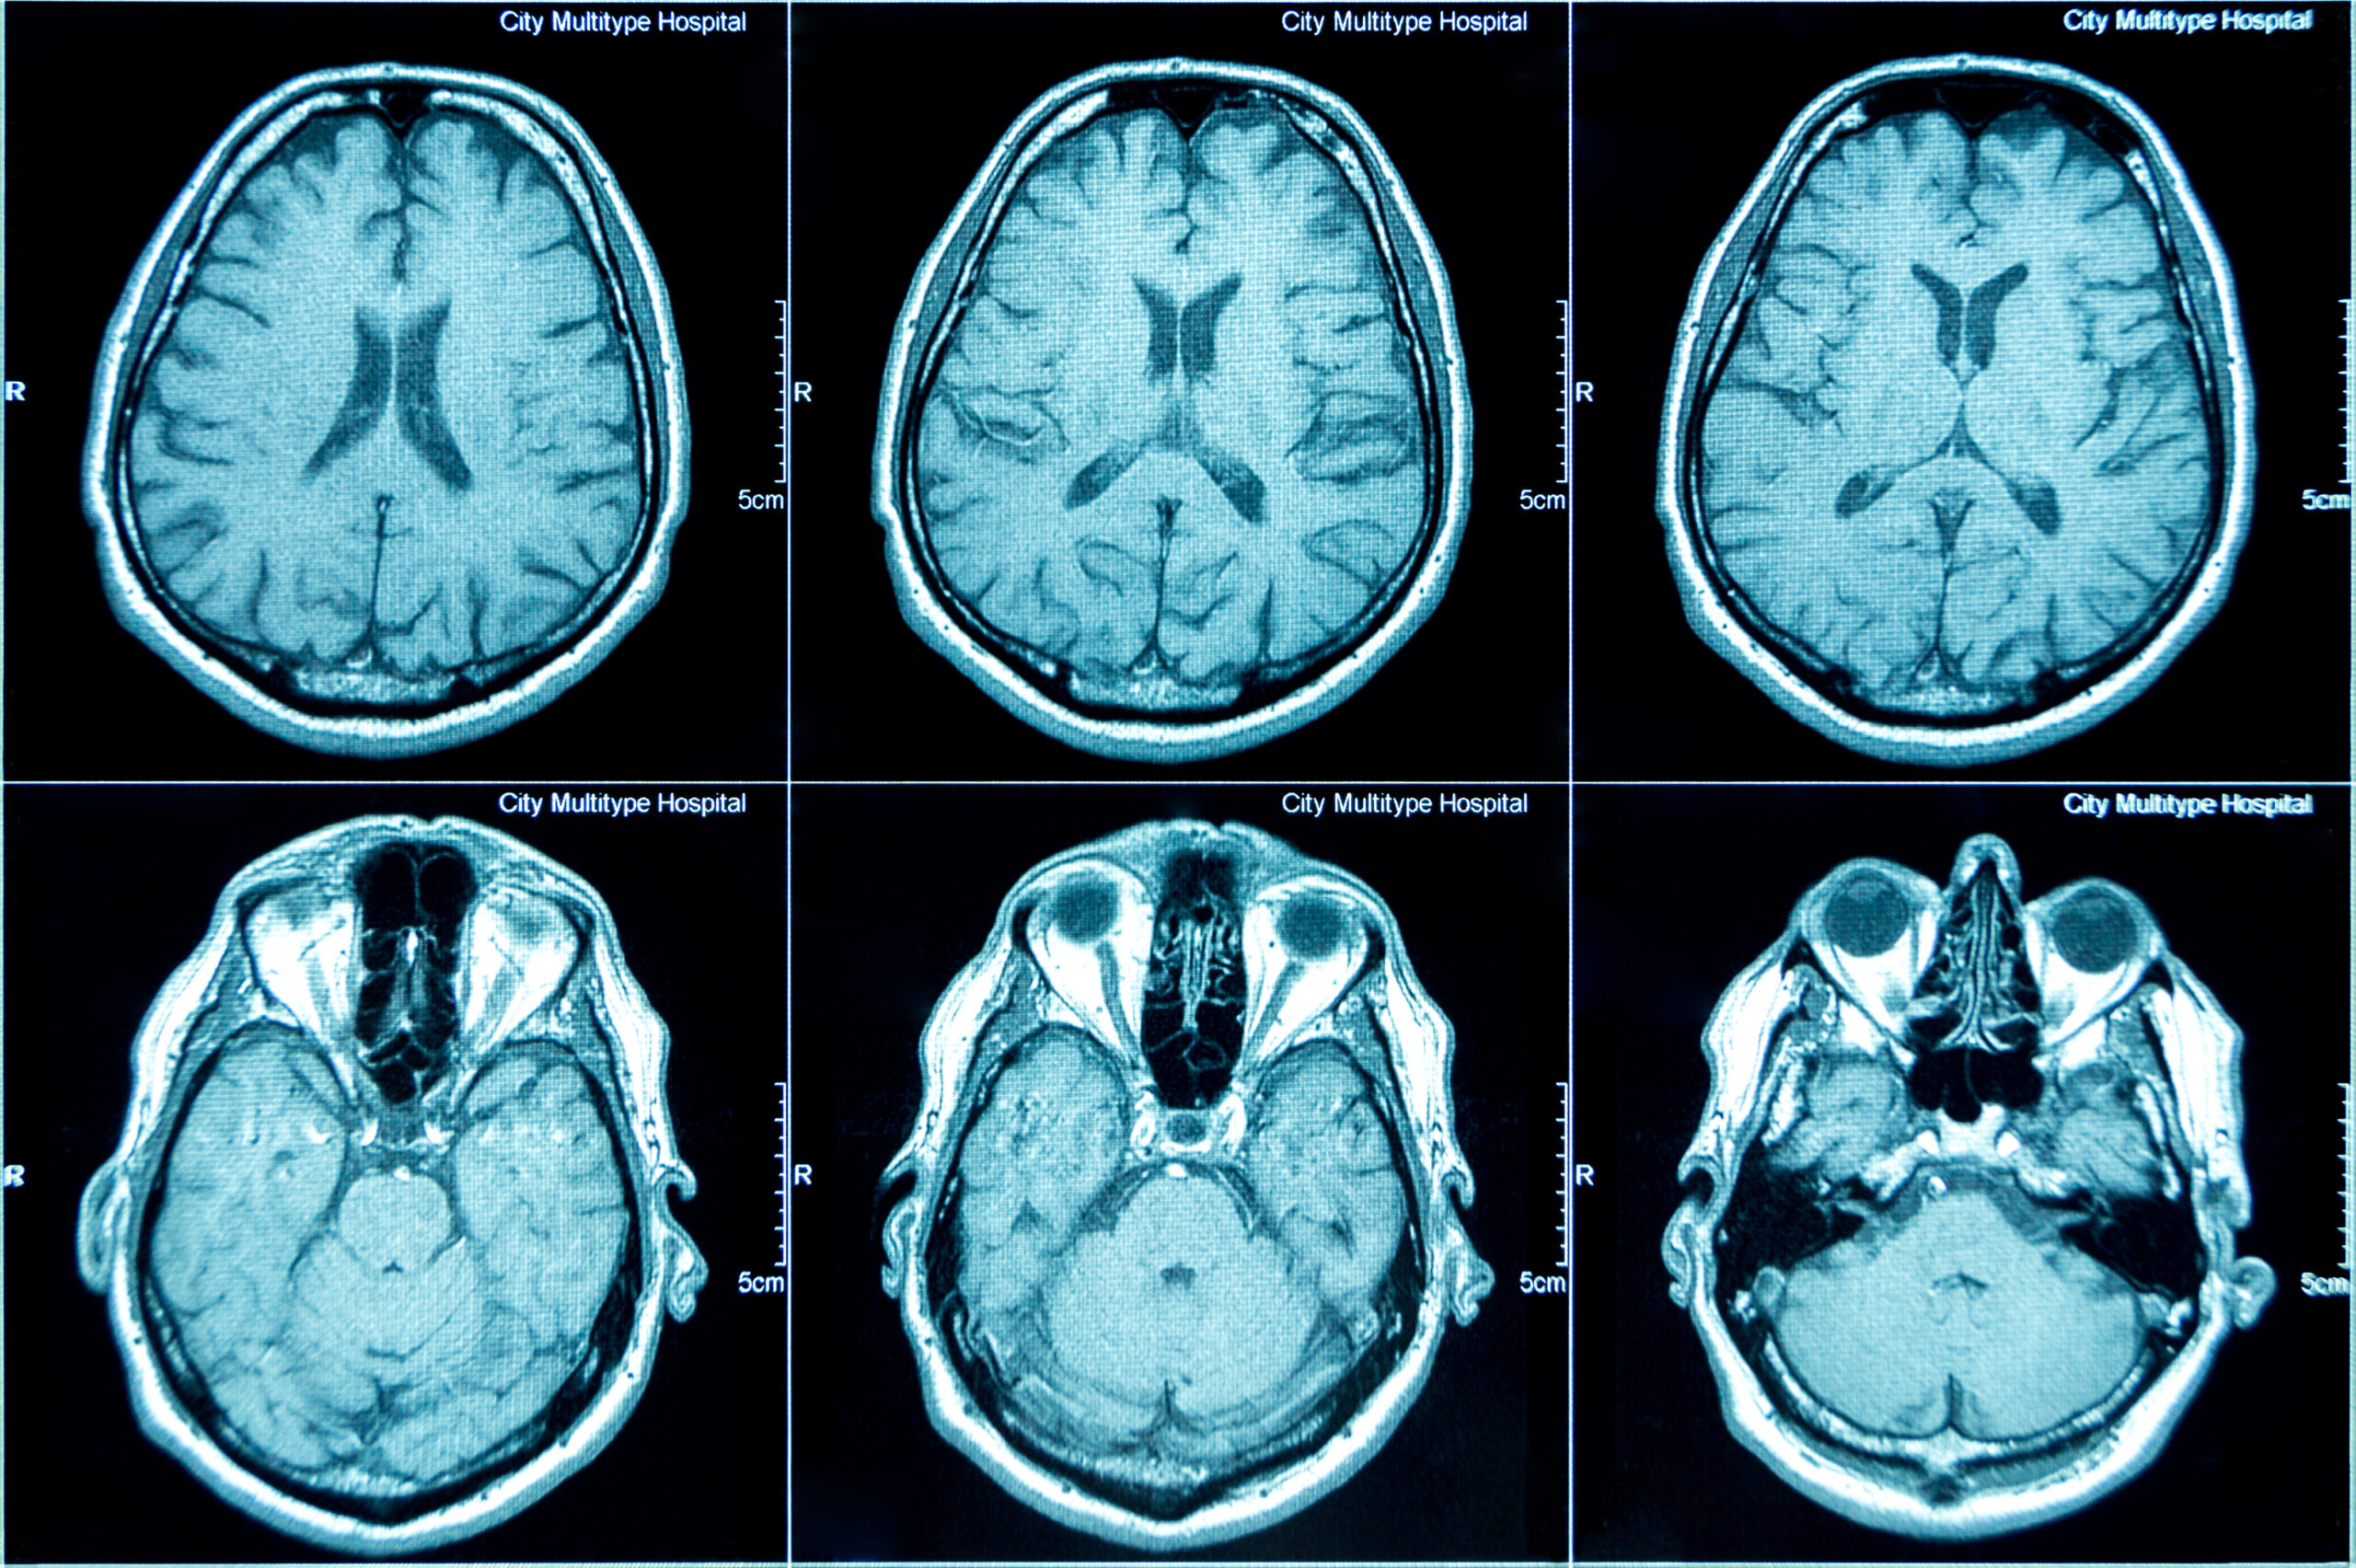

Positron Emission Tomography (PET) is a powerful medical imaging technique used to visualize and quantify physiological processes within the body. Unlike structural imaging methods, such as Computed Tomography (CT) or Magnetic Resonance Imaging (MRI), PET provides functional information by detecting the distribution of biologically active molecules labeled with radioactive isotopes (tracers). After the tracer is administered—typically by injection—it accumulates in specific tissues, and its decay releases positrons. When these positrons interact with electrons in the body, they produce pairs of gamma photons that are detected by the scanner to reconstruct detailed images of metabolic activity, blood flow, or receptor binding.

Multiscale image coregistration aligns images at multiple levels of resolution, beginning with coarse features and progressively refining to finer details. Artificial intelligence enhances this process by learning complex spatial relationships between images, enabling accurate alignment even across different modalities or timepoints. This approach ensures fast, robust, and precise image registration, making it ideal for applications like medical imaging, microscopy, and time-series analysis.